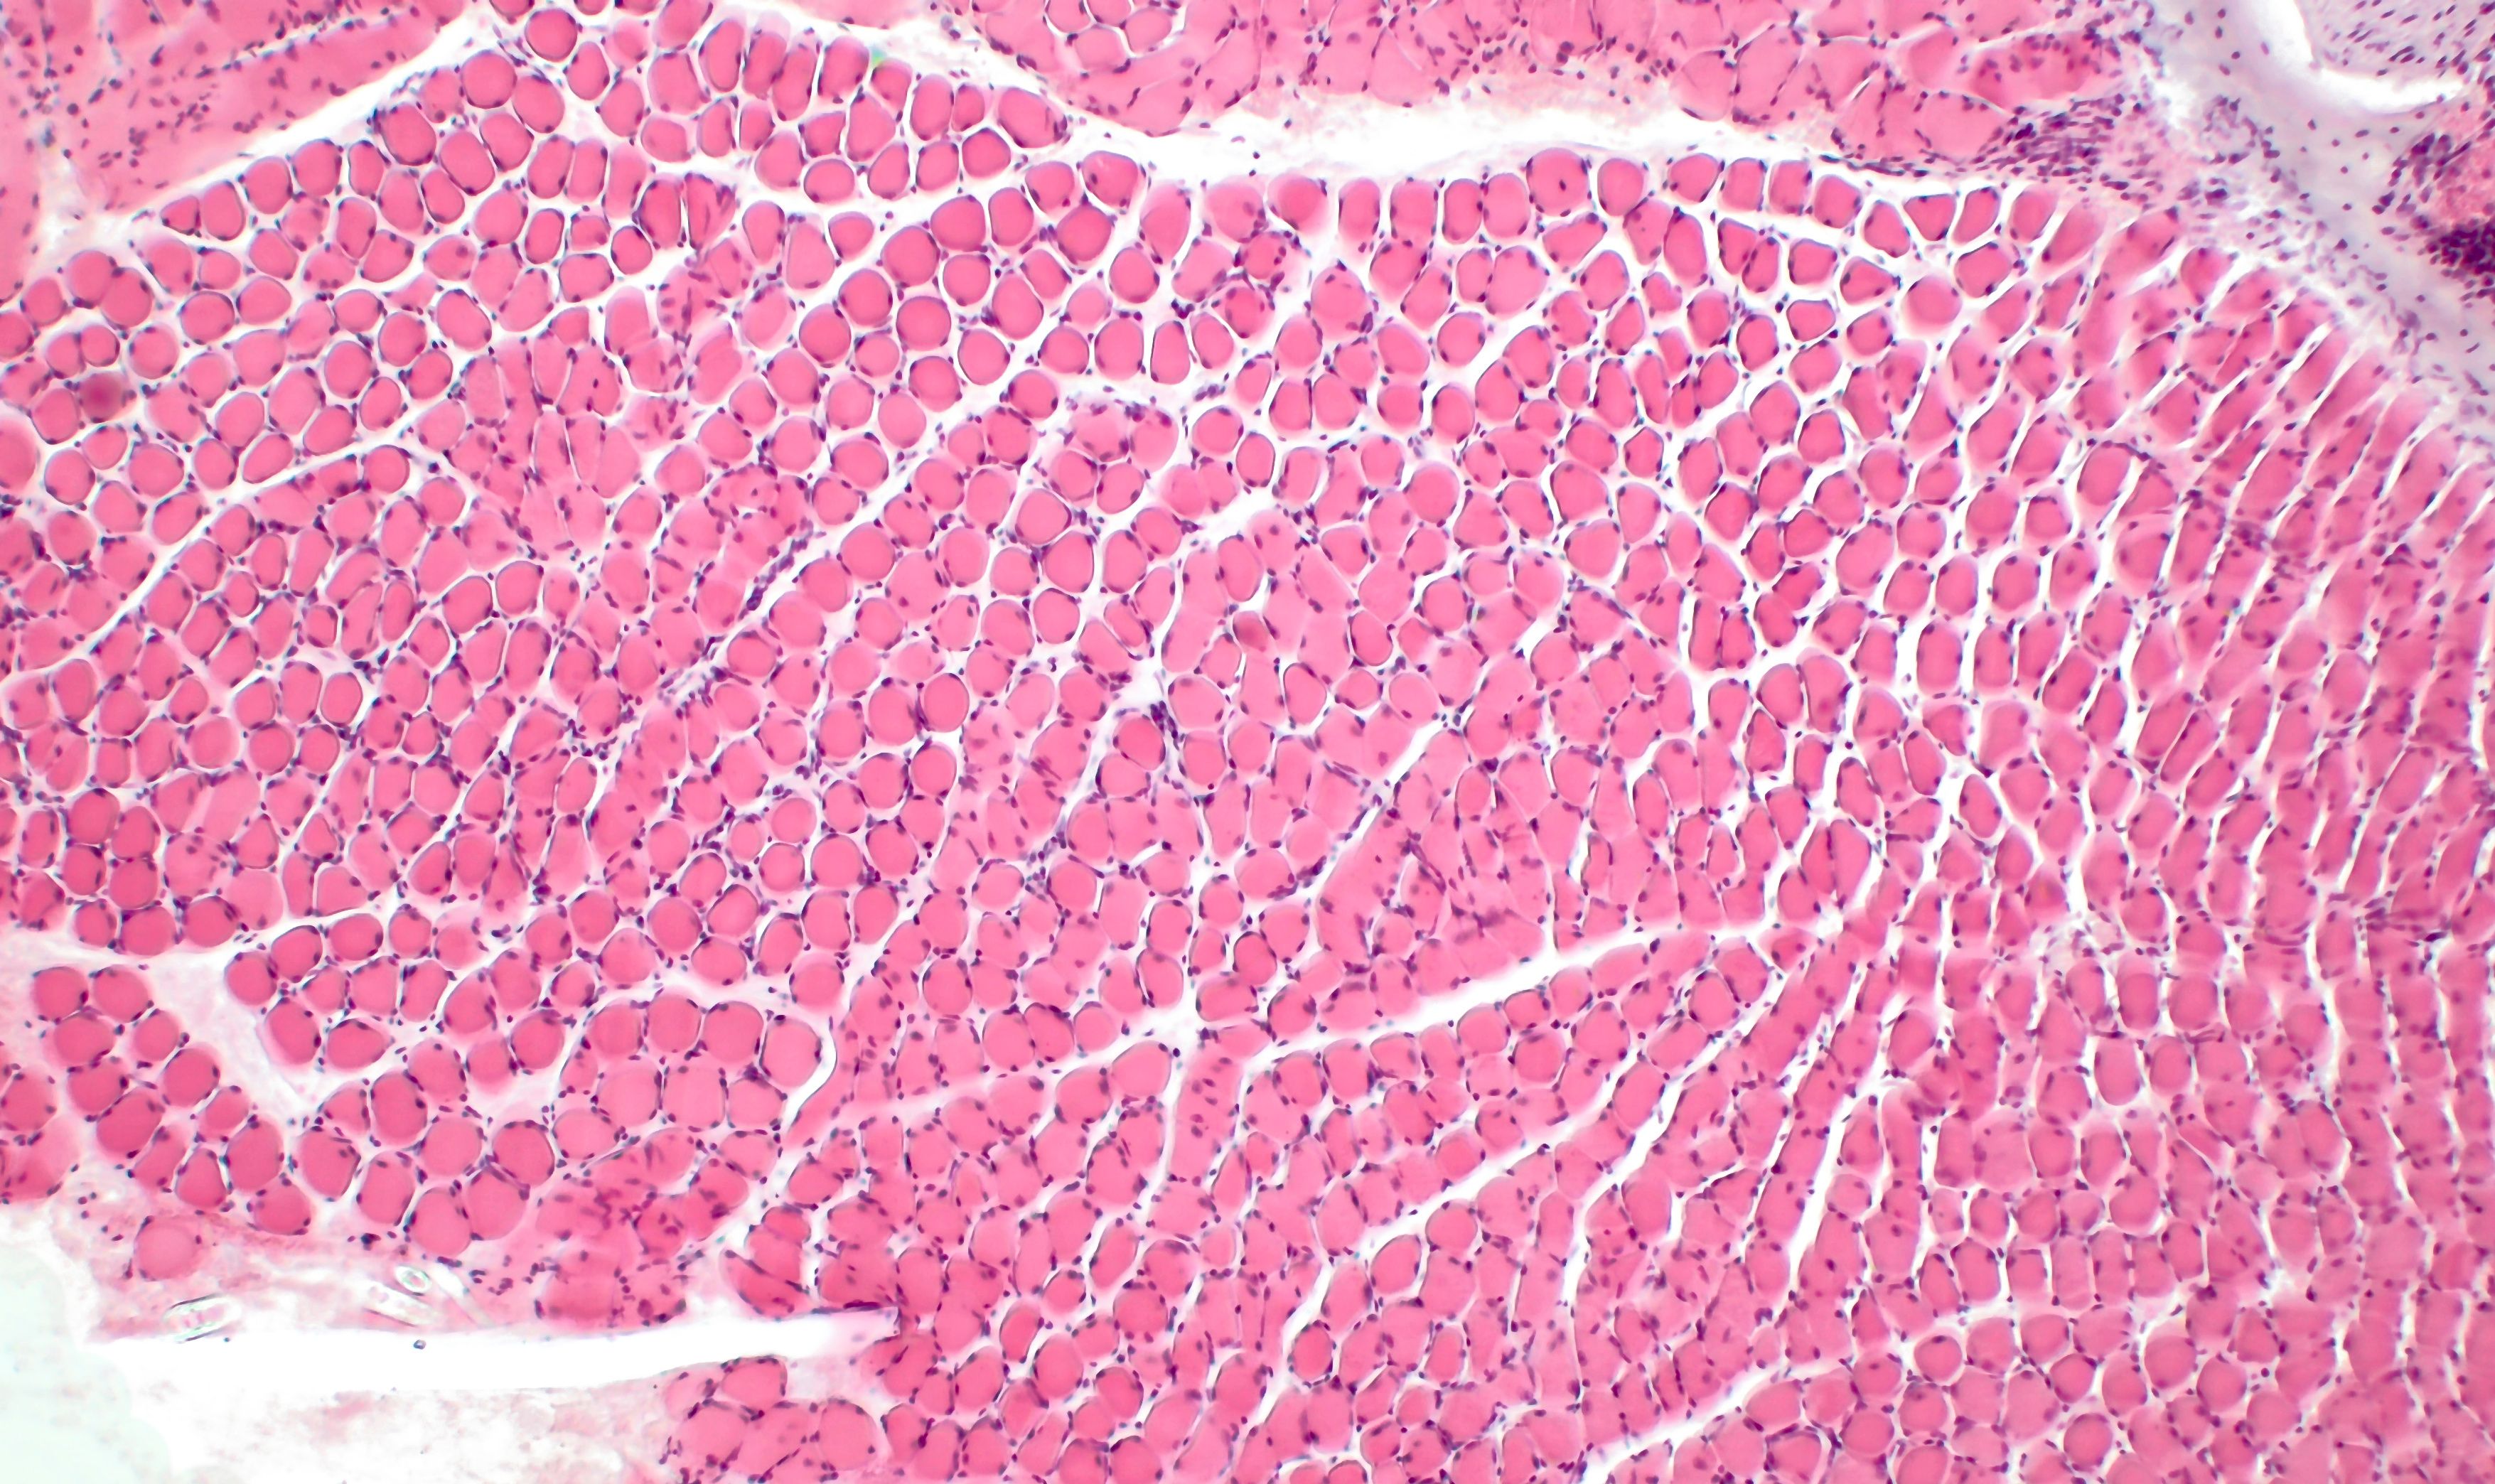

The therapy demonstrated an ability to repair injured muscle in mice models of Duchenne.